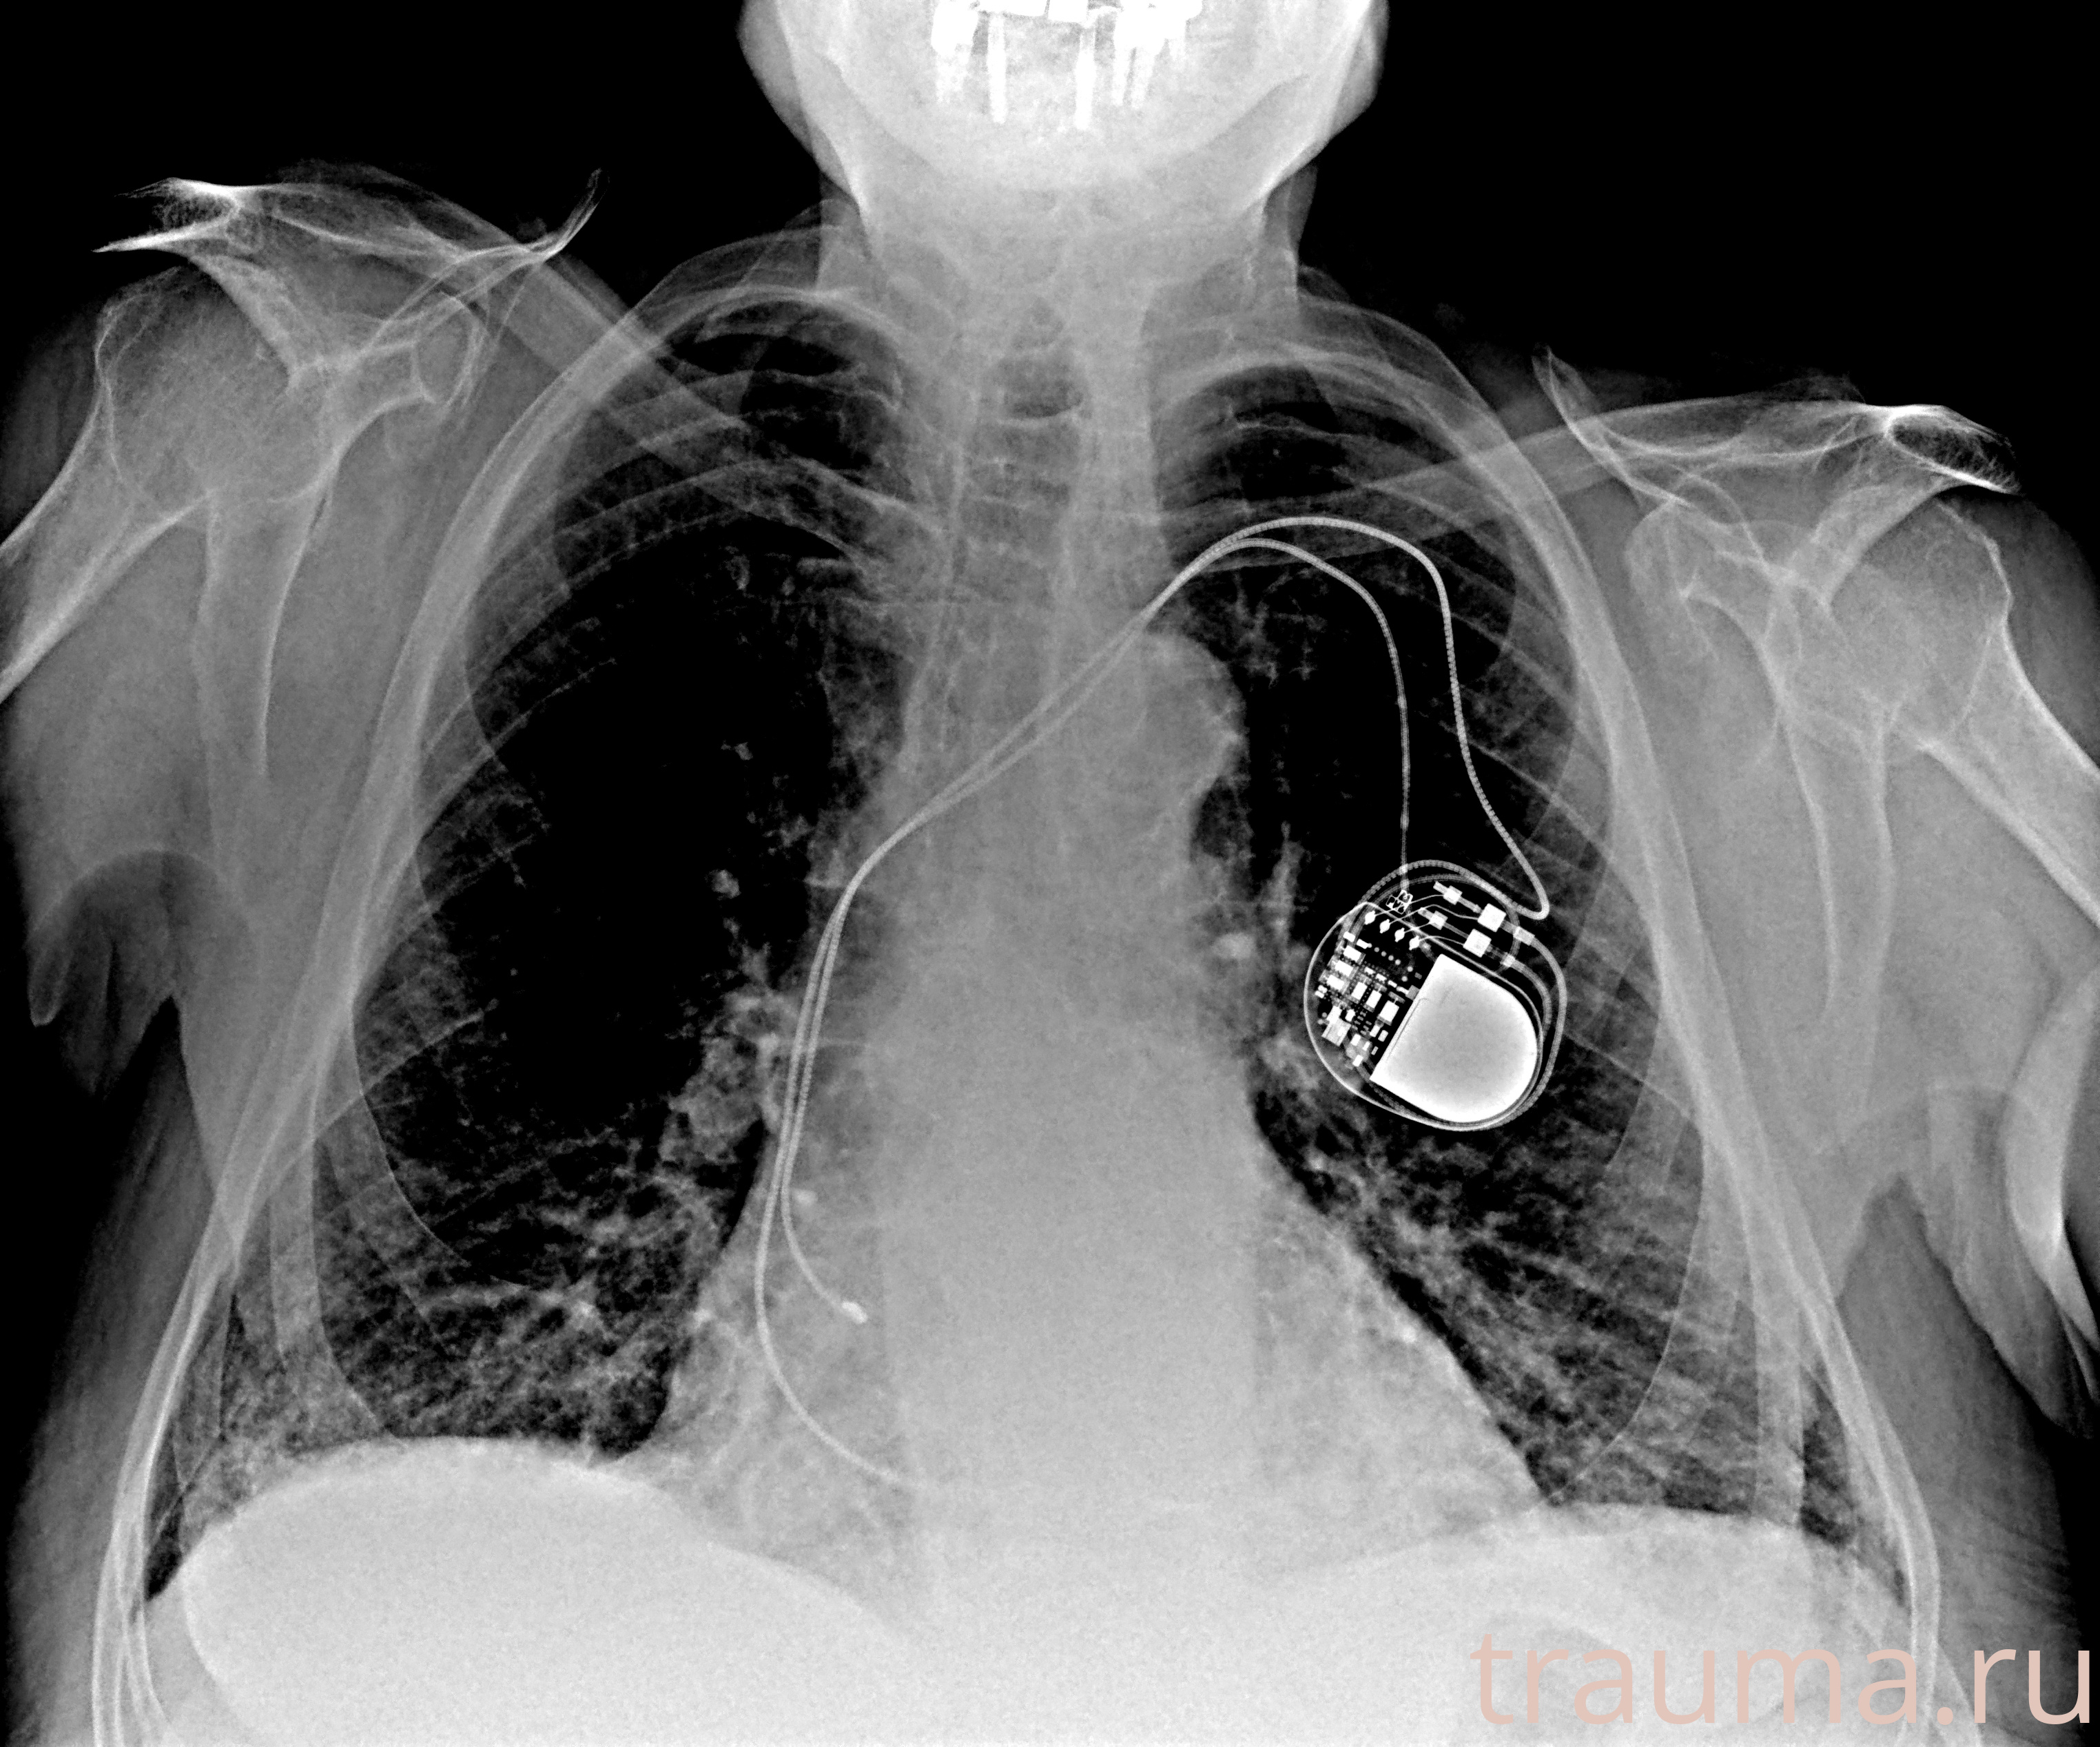

Рентген на дому: по вашему адресу приезжает врач-рентгенолог, травматолог-ортопед с мобильным рентгеновским аппаратом, проводит диагностику травмы или заболевания, делает необходимые рентгенограммы, дает рекомендации по дальнейшему лечению. Получить качественные снимки в домашних условиях возможно благодаря уникальной методике, разработанной МосРентген Центром для института  Склифосовского

при переломе шейки бедра и пневмонии от компании МосРентген Центр - партнера Института имени Склифосовского